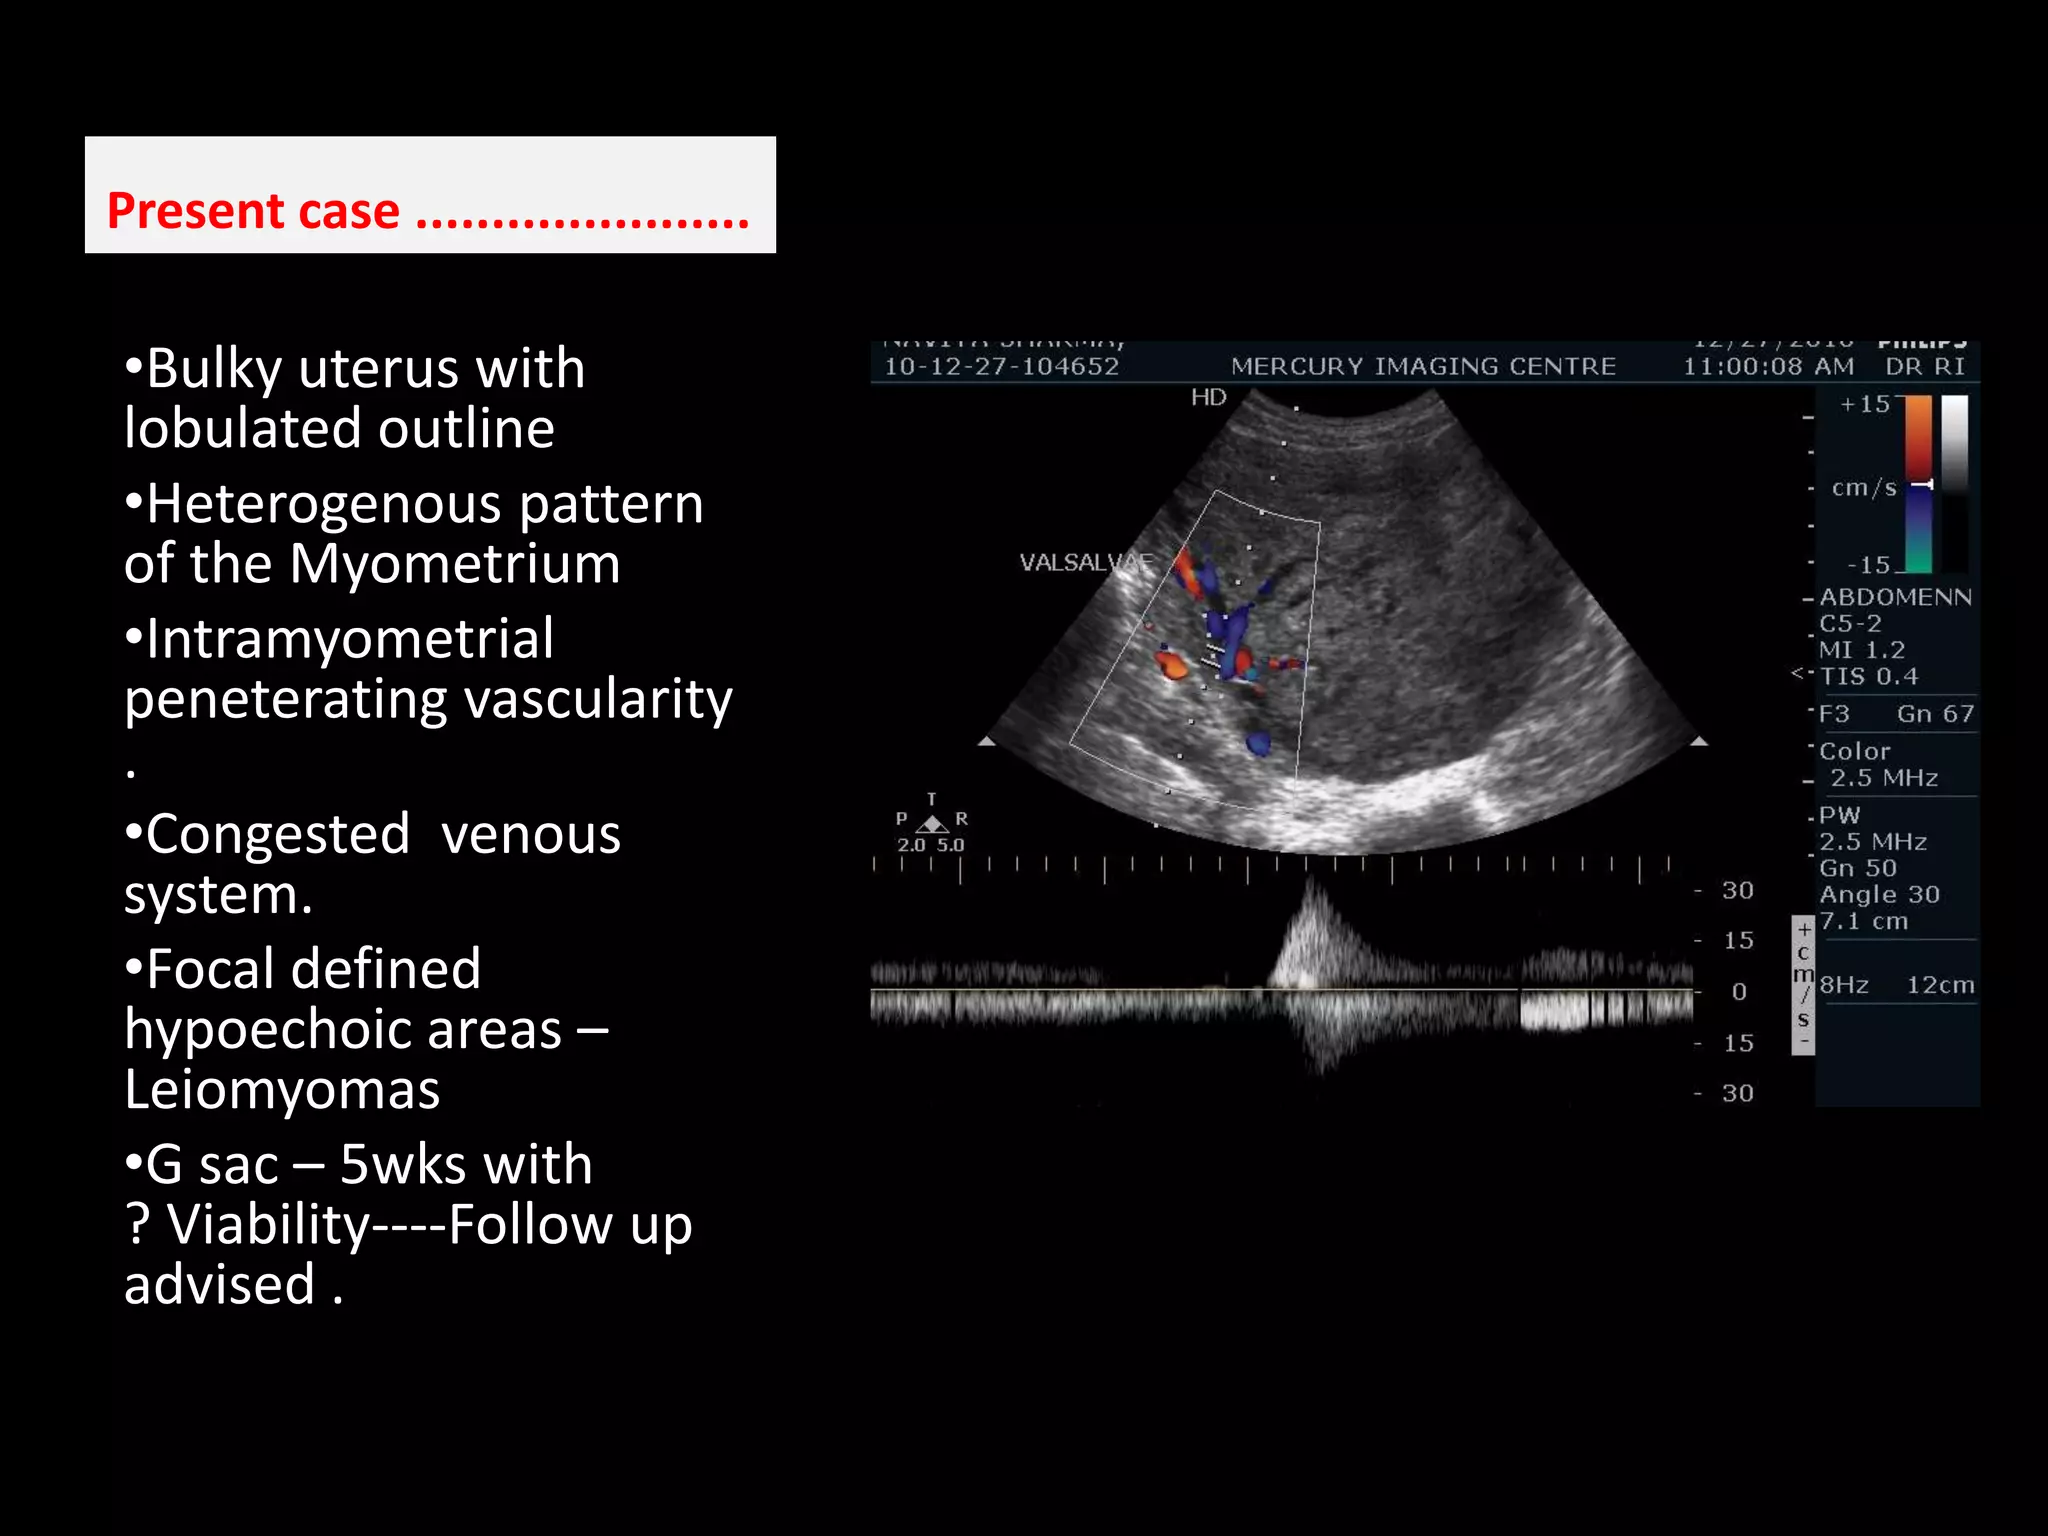

Present case ...................... Bulky uterus with lobulated outline

Heterogenous pattern of the Myometrium

Intramyometrialpeneteratingvascularity.

Congested  venous system.

Focal defined hypoechoic areas – Leiomyomas

G sac – 5wks with                    ? Viability----Follow up advised . INCREASED INTRAMYOMETRIAL   VASCULATURE PENETERATING PATTERN

G sac –5wks with ? Viability----Follow up advised . INCREASED INTRAMYOMETRIAL VASCULATURE PENETERATING PATTERN

VALSALVAE ---- Tortuosvenous channels- normal response. – Pregnanacy with adenomyosis – Associated component of pelvic congestion.